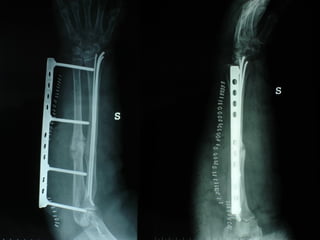

Dal Gennaio 2000 al Dicembre 2005 27 placche LISS di femore

INDICAZIONI COMUNI Fratture sovracondiloidee Fratture intercondiliodee Fratture diafisarie distali PARTICOLARI Fratture con grave osteoporosi Fratture periprotesiche

VANTAGGI CHIRURGIA MININVASIVA Mini Open Inserimento della placca sottocutaneo per scivolamento Viti percutanee Preservazione dei tessuti molli Ridotto danno vascolare Rapida ripresa funzionale

F, 68 y

LISS  NCB

NCB

Conclusioni Riduzione  anatomica Minimo trauma chirurgico Corretto equilibrio fra elasticità e stabilità Precoce mobilizzazione